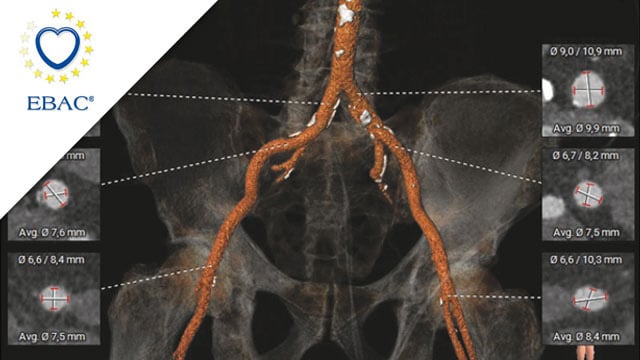

LAA closure with CT planning: challenging inferior chicken wing morphology

A 77-year-old woman with paroxysmal AF and prior GI bleeding is referred for LAA closure, but CT reveals a shallow, inferior chicken-wing morphology that complicates device selection and planning. How would you treat?